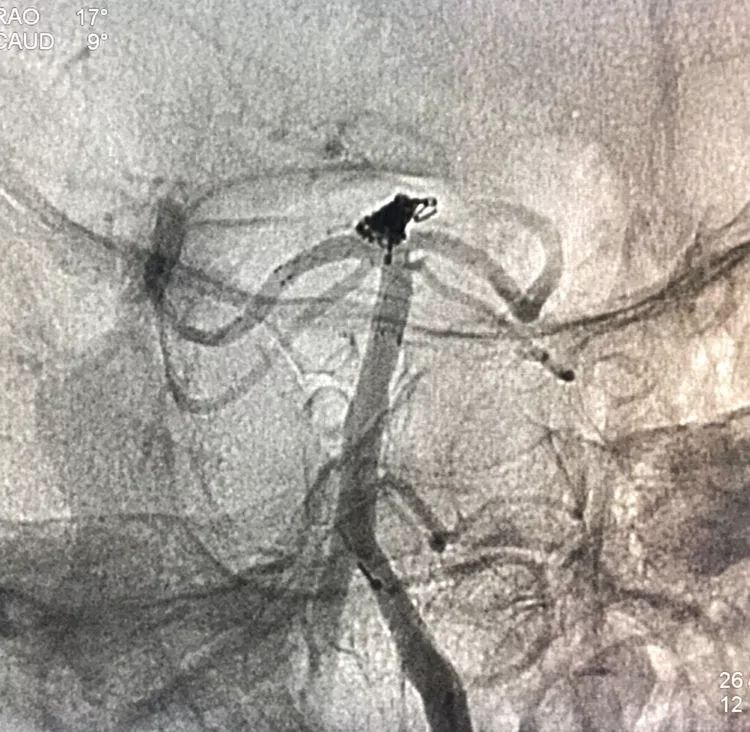

回到工作位造影,显示基底动脉顶端动脉瘤完全栓塞,基底动脉顶端四根血管畅通。

术后左椎动脉正位、侧位的造影和蒙片